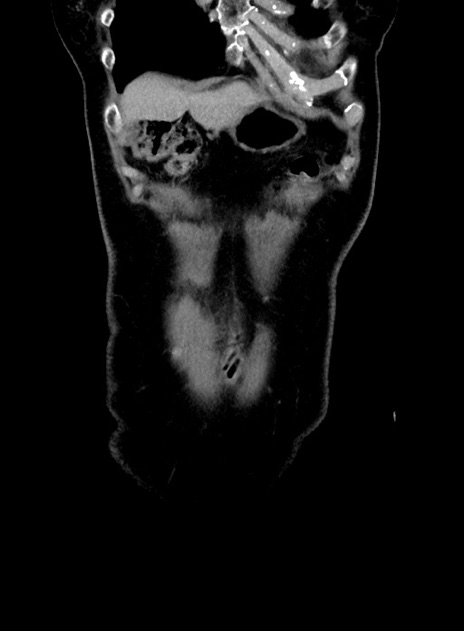

症例9(冠状断像)

症例

【症例】 60歳代女性

【主訴】むかつき、みぞおちの痛み

【現病歴】3日前よりむかつきがあり、食事がとれない。

【既往歴】糖尿病

【身体所見】発熱なし、心窩部圧痛軽度あるも、腹膜刺激症状なし。

【データ】WBC 7400、CRP 1.92